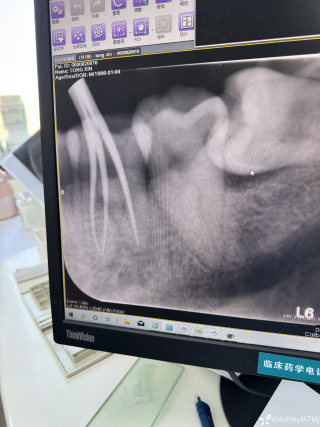

病例信息【患者信息】:男、16岁【主诉】:全身皮肤瘙痒伴皮疹10分钟【现病史及既往史】:10分钟前患者骑摩托车行驶途中,突感全身瘙痒,奇痒无比伴全身发热,心跳加快。急诊就诊,既往无类似病史,否认咽喉梗阻感、胸闷、气短、呼吸困难、恶心、呕吐、腹泻、乏力等不适。【检查】:血压:138/80mmHg,心率:116次/分,呼吸:21次/分。【临床诊断】:急性荨麻疹【治疗经过及结果】:给予吸氧、肌注扑尔敏1支,口服氯雷他定1片,静滴甲泼尼龙40mg后瘙痒明显减退,皮疹消失。病例讨论双手十指及双足未纹身,护士最后穿刺左手大拇指。